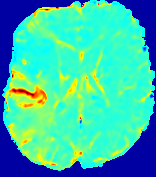

LesionRefer to captionRefer to captionRefer to captionRefer to captionRefer to captionRefer to caption𝐕rgbsubscript𝐕𝑟𝑔𝑏{\bf{V}}_{rgb}Refer to captionRefer to captionRefer to captionRefer to captionRefer to captionRefer to caption𝐕2subscriptnorm𝐕2{\|\bf{V}}\|_{2}Refer to captionRefer to captionRefer to captionRefer to captionRefer to captionRefer to captionRefer to caption3.53.53.52.82.82.82.12.12.11.41.41.40.70.70.70.00.00.0(mm/s)𝑚𝑚𝑠(mm/s)D𝐷DRefer to captionRefer to captionRefer to captionRefer to captionRefer to captionRefer to captionRefer to caption0.0200.0200.0200.0160.0160.0160.0120.0120.0120.0080.0080.0080.0040.0040.0040.0000.0000.000(mm2/s)𝑚superscript𝑚2𝑠(mm^{2}/s)Slice #1Slice #2Slice #3Slice #4Slice #5Slice #6

Figure 4: PIANO feature maps for another patient in the ISLES 2017 training set, where the lesion is located in the right hemisphere. Top row: segmented stroke lesion region (white) on different slices. The corresponding slices for the PIANO feature maps are shown in the following rows.

For a better insight into an estimated velocity field 𝐕𝐕{\bf{V}} and diffusion field 𝐃𝐃{\bf{D}}, we compute the following maps: (1) 𝐕rgbsubscript𝐕𝑟𝑔𝑏{\bf{V}}_{rgb}: Color-coded orientation map of 𝐕=(Vx,Vy,Vz)T𝐕superscriptsuperscript𝑉𝑥superscript𝑉𝑦superscript𝑉𝑧𝑇{\bf{V}}=(V^{x},V^{y},V^{z})^{T}, obtained by normalizing 𝐕𝐕{\bf{V}} to unit length and mapping its 3 components to red, green, blue respectively; (2) 𝐕2subscriptnorm𝐕2\|{\bf{V}}\|_{2}: 222 norm of 𝐕𝐕{\bf{V}}; (3) D𝐷D: scalar field in Eq. 5.

Fig. 3 and Fig. 4 show the PIANO feature maps estimated from two ISLES 2017 patients: all are highly consistent with the lesion in both cases. Details of the blood flow trajectories are revealed in 𝐕rgbsubscript𝐕𝑟𝑔𝑏{\bf{V}}_{rgb} by the ridged patterns and the sharp changes of colors in the unaffected (right) hemisphere, while the flat patterns appearing within the lesion provide little directional information about the velocity and indicate low velocity magnitudes. Velocity magnitudes are more directly visualized via 𝐕2subscriptnorm𝐕2\|{\bf{V}}\|_{2}, from which one can easily locate the lesion where 𝐕2subscriptnorm𝐕2\|{\bf{V}}\|_{2} is low. D𝐷D also indicates lower diffusion values in the lesion, though with less contrast potentially due to the fact that it captures the accumulated effect of CA diffusion at the voxel-level.